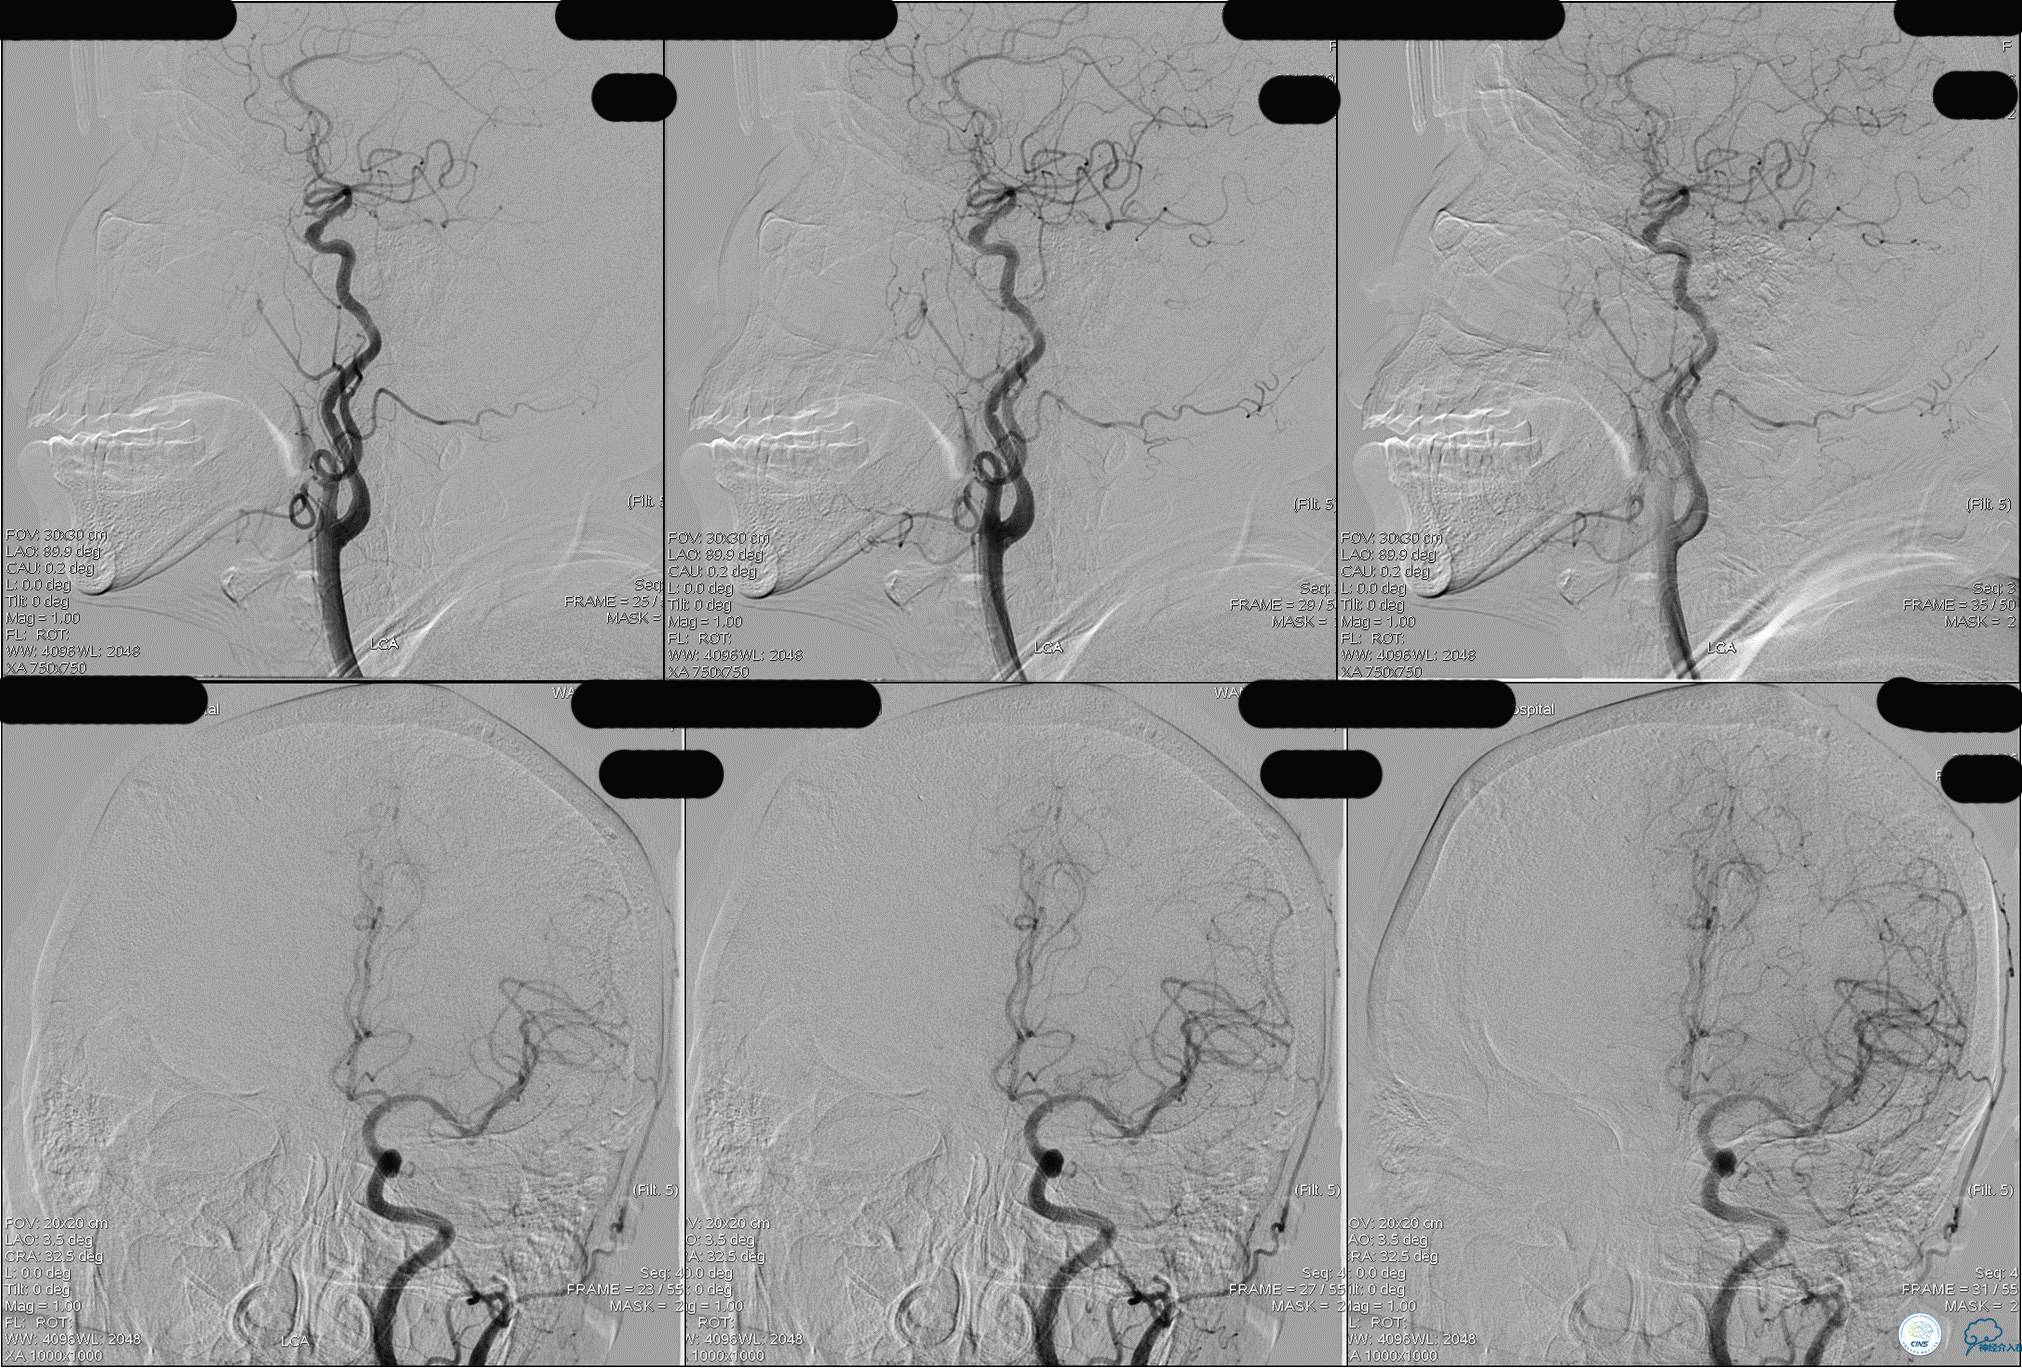

发病5.5小时给予股动脉穿刺

发现股动脉入路很差,考虑经桡穿刺。

》DSA资料(左侧颈动脉)

》DSA资料(经桡动脉,5F导引导管)

》DSA资料(前2次取栓,未取出,soli 4-20)

》DSA资料(第3次取栓)

第3次取出血栓

》DSA资料(第3次取栓后,发病10h)

》DSA资料(观察30min后,左椎造影)

★基底动脉尖端的血栓偏向哪侧,应该将Solitaire支架放入同侧的大脑后动脉,这样取栓的成功率较高一些。